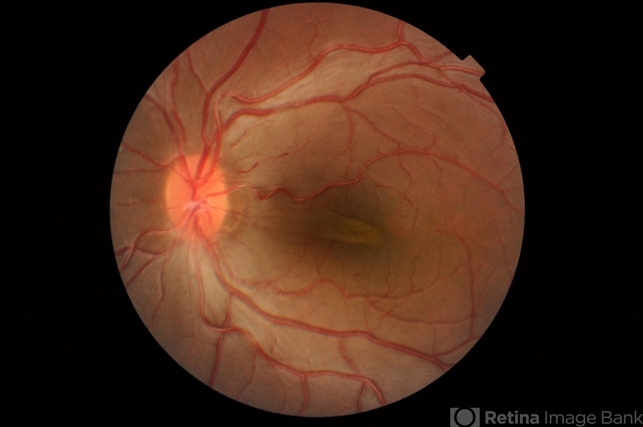

- macular fold, High Hyperopia

- Fundus Photograph of Left eye of a 17-year old Female Macular Folds with High Hypermetropia